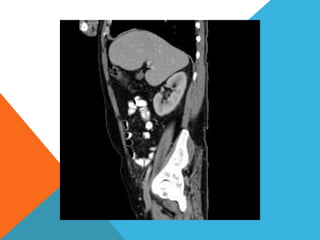

El paciente presentó síntomas de sangrado digestivo y pérdida de peso. Exámenes revelaron gastritis crónica asociada a H. pylori. Un tumor fue descubierto en una colonoscopia normal. La cirugía removió un tumor fibroide solitario, una rara neoplasia mesenquimal que usualmente crece lento y tiene bajo potencial de malignidad. El pronóstico después de la remoción quirúrgica es generalmente bueno.